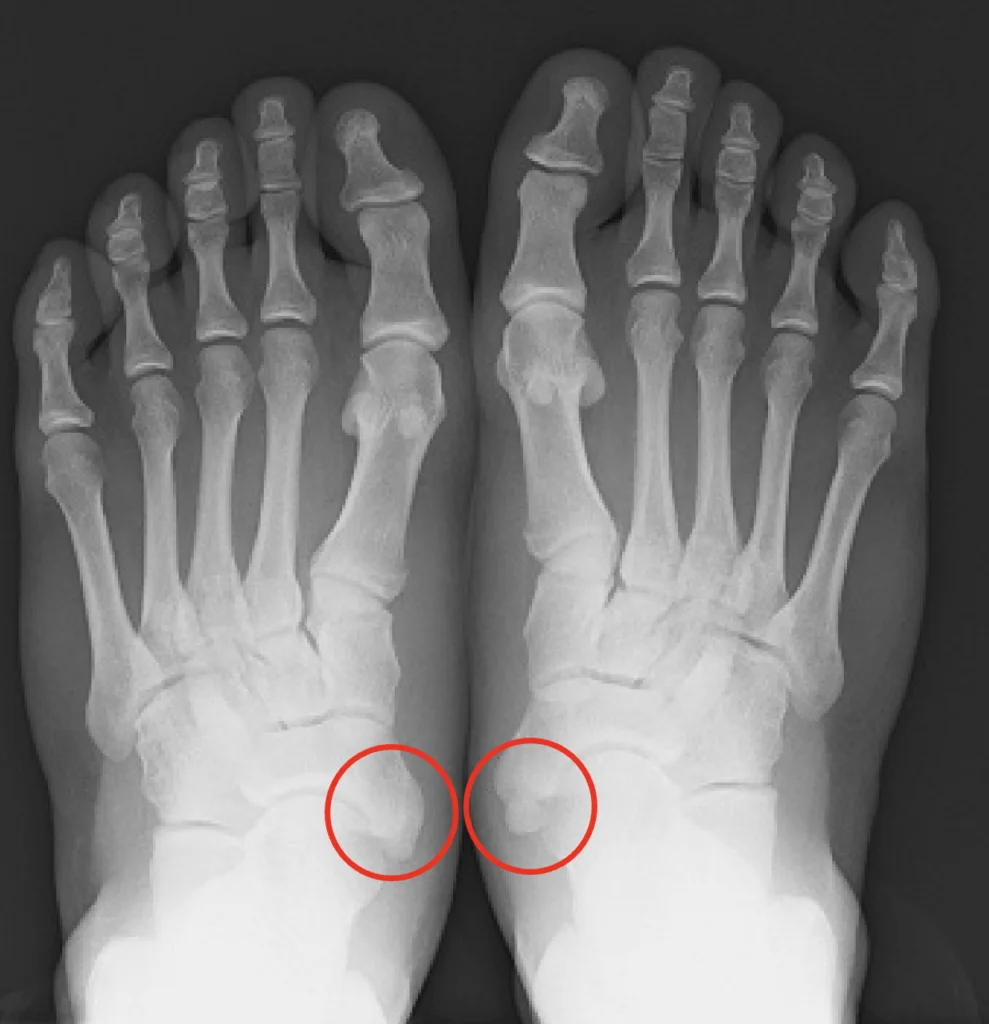

外脛骨の分類には、Veitch(バイチ)分類により評価されます。

TypeⅠ:舟状骨本体とは連続性を持たず円形もしくは楕円形を呈す。(基本的に症候性にならない)

TypeⅡ:舟状骨の明確な一部分ですが、舟状骨結節は幅2mm未満の不規則な輪郭の線維軟骨部によって分離される。

TypeⅢ:外脛骨が骨性癒合し、舟状骨の内側の大きな隆起となっているもの。

レントゲン写真ではこのように映ります(左:TypeⅢ 右:TypeⅡ)。